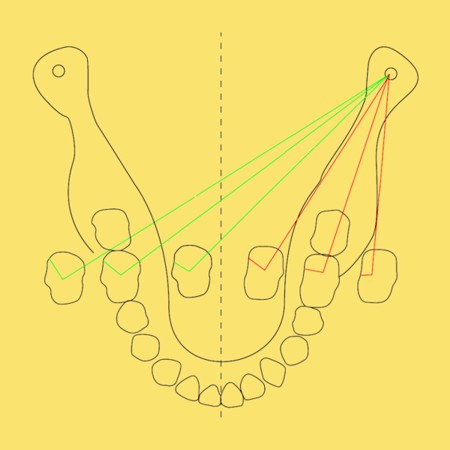

Primera Parte RESUMEN: La alta complejidad inherente a los procedimientos de Rehabilitación Oral, obligan al profesional que la ejerce a basarse en parámetros multidisciplinarios, a veces lo suficientemente intrincados que hacen imposible la práctica de la misma, sin la presencia en su mente de una clara concepción de la Oclusión. The extreme complexity of Oral Procedures, make it imperative for the working professional to rest on multidisciplinary parameters, sometimes so complex that make impossible its practice without the presence of a clear idea of Oclusion. DESARROLLO Suele ser sumamente árido el abordaje de un tema como Oclusión, desde la perspectiva de nuestro diario trabajo ,con todo el strees que este conlleva, con toda la lucha que significan citas, honorarios, diferentes personalidades de los pacientes, inquietudes de los mismos, etc. «LA MEJOR OCLUSIÓN ES LA QUE TIENE LA MEJOR DESOCLUSIÓN» Básicamente, podemos como desde hace ya muchos años se viene haciendo; clasificarlos en: A)Determinantes Posteriores (fijos) Más contemporáneamente, en: I-Mecanismos Primarios: A.T.M. GUIA ANTERIOR INCLINACIÓN DEL PLANO OCLUSAL CURVA SAGITAL DE SPEE FORMA DE LA ARCADA III-Mecanismos Elementales CRESTAS TRIANGULARES INTERNAS Analicemos cada uno de ellos: Es evidente, que la reproducción de las características de la A.T.M., en nuestro aliado fundamental, el Articulador; es imprescindible. Partiendo de la premisa de obtener una OCLUSIÓN MUTUAMENTE PROTEGIDA, para luego arribar al concepto de OCLUSIÓN MUTUAMENTE COMPARTIDA, concepto este que desarrollaremos durante el transcurso de las distintas entregas, analizaremos cada uno de los FACTORES DETERMINANTES DE LA OCLUSIÓN. El primero de ellos, por ser fijo e invariable, solo diremos que: son sus INCLINACIONES PLANARES, o sea : A-INCLINACIÓN DE LA TRAYECTORIA CONDILEA C-BENNET INMEDIATO articuladores totalmente ajustables) D-DISTANCIA INTERCONDILAR. En cuanto a la GUÍA ANTERIOR, mecanismo primario y por supuesto anterior, provee al cuerpo mandibular; del camino a recorrer durante las excursiones protrusivas y lateralidades, a través del vínculo entre las piezas dentarias anteriores, superiores e inferiores. En un corte sagital, podemos observar la relación entre estos donde vemos que se vinculan sin entrar en un contacto franco, sino más bien en una relación de vencindad muy intima a la que llamamos: PUNTO DE ACOPLAMIENTO. Otros factores fundamentales de la GUÍA ANTERIOR son : A-ALTURA FUNCIONAL B-PUNTO DE ACOPLAMIENTO En cuanto a los SURCOS, sabemos que durante una Transtrusión, las cúspides fundamentales generan surcos sobre las piezas que antagonizan. Dichos surcos proveen de una vía de escape a las cúspides antagonistas para evitar colisiones, con las indeseables fuerzas laterales cuya gravedad ya conocemos. MECANISMOS SECUNDARIOS La CURVA FRONTAL DE WILSON, se observa invertida a nivel de los caninos y de los primeros premolares. El PLANO OCLUSAL, en realidad no es ningún plano, sino la sumatoria de muchos MICROPLANOS, los cuales individualmente pueden constituir factores presentes en la OCLUSIÓN, pero auténticos problemas para la DISCLUSIÓN. La CURVA SAGITAL DE SPEE, denominada originariamente de BALKWIL-SPEE, fue concebida como una curva. El cuarto factor SECUNDARIO: el ANCHO DE LA ARCADA, es evidente que variando los ejes de rotación , alrededor de las diferentes distancias ;cambiará la dirección de los escapes (surcos), de los elementos que en el se muevan (cúspides). MECANISMOS ELEMENTALES Los CUATRO NIVELES DE OCLUSIÓN y las CRESTAS TRIANGULARES INTERNAS, constituyen de por si, la herramienta ejecutora de las funciones gnáticas. A- ELEVACIONES 1-Puntas Cuspídeas B-DEPRESIONES 1-Fosas SURCOS DE DESARROLLO De las CRESTAS TRIANGULARES INTERNAS, acentuamos su importancia en ellas dado que son las efectoras finales de la molienda, y su triangularidad debe tener su base partiendo del surco y su vértice terminando en la Punta Cuspídea, condición importante para evitar colisiones durante la transtrusión (movimiento de lateralidad ). EFECTOS DE LA VARIABILIDAD DE LOS FACTORES DETERMINANTES DE LA OCLUSÍON Cada uno de los determinantes influye aumentando o disminuyendo tanto la DESOCLUSIÓN como la ALTURA CUSPÍDEA INCLINACIÓN DE LA TRAYECTORIA SAGITAL INCLINACIÓN DEL PLANO OCLUSAL RADIO DE CURVATURA DE LA ÁNGULO DE LA TRAYECTORIA ALTURA DEL PUNTO DE LATERO SURTRUSIÓN / MOV. DE BENNET INMEDIATO CURVA FRONTAL DE WILSON SURCOS BIBLIOGRAFÍA Dibujos y esquemas tomados del libro: Oclusión Orgánica…un camino hacia la Rehabilitación Oral. 1)William Mc Horris,B.S.,D.D.S. Oclusión. Con especial énfasis sobre :El rol funcional y parafuncional de los dientes anteriores. 2)Von Spee , Craff(Anatomista alemán, describió la curva de compensación de la articulación de molares y premolares).CURVA DE SPEE 1.89 3)Stuart,D.»Some aspects of the inervation teeth.»Procedings of Royal Society of Medicine.20:1675,19274)Muhleman,H. y Savdir,S»Tooth movility-its causes and significance»Journal of Periodontology ,36:153,Marzo ,Abril,1965. 4)Muhleman,H. Y Savdir,S»Toothmovility its causes and significance» Journal of Periodontology,36:153,marzo,abril,1965. 5-Oclusión y Diagnóstico en Rehabilitación Oral. 6-Anatomia Odontológica. -A contribution to the study of the movementes of the mandible. 8-Celenza F.W, Nadeskin J.F.,Oclusión.Situación actual. 9-D´Amico 10-Dawson P.E. 11-Huffman -Regenos. 12-Hobo S.-Takayama H.A. 13-Lucia V.O 14-Mc Horris. 15-Mc Horris. 13-Posselt U. 16-Stuart C. 17-Vartan Veshnilian

C)Determinantes Anteriores (variables)SURCOS

Estos no son otra cosa que Arcos Góticos que adoptan distintas orientaciones según el lado hacia el cual se mueve la mandibula, y su angulación dependerá de la distancia a que se encuentren del eje vertical alrededor del cual roten.

Estos surcos reciben el nombre de :TRABAJO, NO TRABAJO y PROPULSIÓN ,según la acción ejercida por la cúspide.

Los surcos de Trabajo (ST)en rojo, No Trabajo (SNT) en verde, y Propulsión (SP) en azul, provéen de vías de escape a las cúspides durante la Transtrusión.